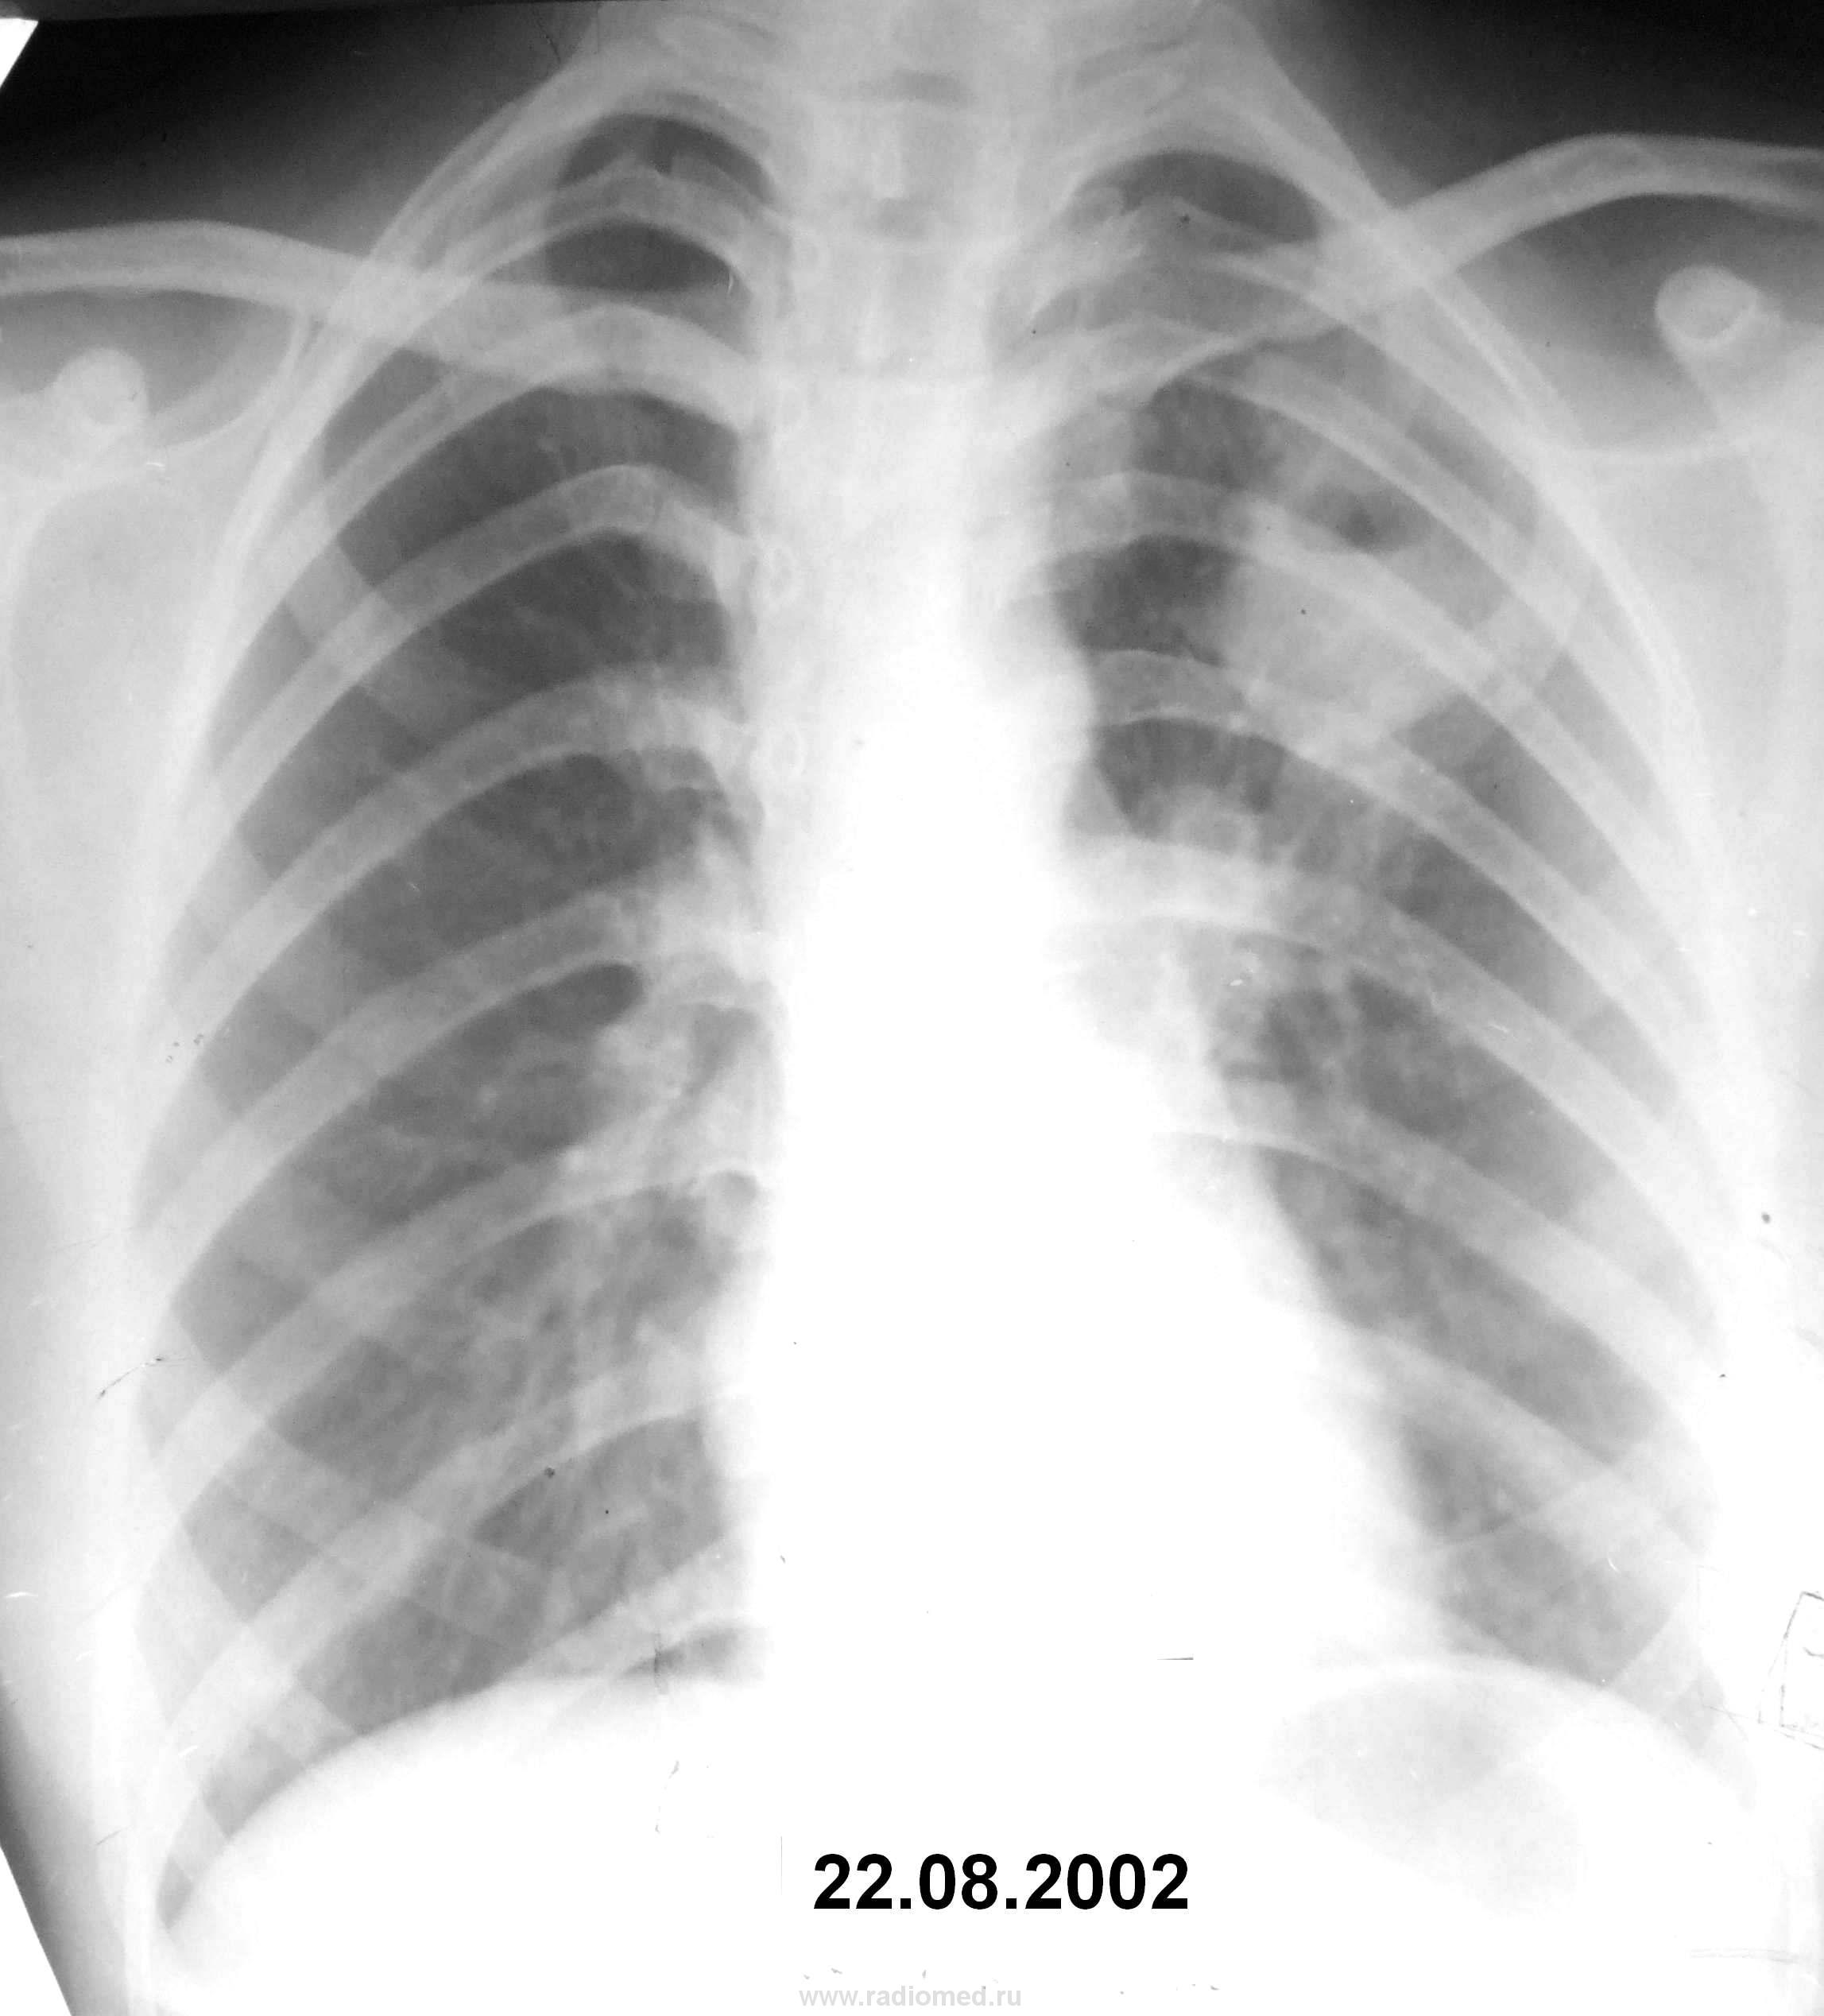

Вчера перед отходом с работы решил снять и показать Вам снимки. Болезнь верифициорвана. Всего снимков 3 в динамике. Как всегда гостей у нас тьма. Может кто-то из них зарегистрируется и скажет свое веское слово. Итак, какое заболевание Вы предполагаете, глядя на свои мониторы. Смотрите очень внимательно. Лучше написать одно заболевание, но не более 2-х. Пишите друзья. С уважением Nikolas

Уважаемые коллеги! Привожу результаты обследования больной, имеющиеся в моем распоряжении.

Пациентка 19 лет. Студентка. Контакт с больными туберкулёзом не установлен. Заболела остро в мае мес. 2002 года. По поводу «острого респираторного заболевания» ей в амбулаторных условиях проведено лечение сульфаниламидными препаратами. Самочувствие улучшилось. В начале августа вновь повысилась температура тела до субфебрильных цифр. В течение 10 дней пациентке проведено лечение амоксициллинином. После рентгенологического исследования органов грудной клетки (22.08.2002 г) пациентку сразу госпитализировали в ПТД. При поступлении в стационар предъявляла жалобы на кашель с выделением небольшого количества слизистой мокроты. Температура тела 37,4 С, состояние удовлетворительное. Гемограмма: лейкоциты – 9,6 *109/л, СОЭ – 25 мм/ч. Бронхоскопия: на стенке левого верхнедолевого бронха обнаружен инфильтративный туберкулёз. Повторно после бронхоскопии выполнена рентгенограмма органов грудной клетки в передней прямой проекции (см. рисунок 2). Реакция на пробу Манту с 2 ТЕ ППД-Л – 21 мм. При исследовании трех проб мокроты методом посева получен рост МБТ. Больная состояла на учете в ПТД. Представляю рентгенограмму через 4 года от 18.02.2006 г. (см. рисунок 3). Других материалов нет. Данное клиническое наблюдение ещё раз подтверждает клинико-рентгенологическое многообразие проявлений туберкулёзного процесса. Точное и уверенное заключение дал коллега Петрович. Предложил нам хорошие ссылки. Просите Петровича поделиться с Вами, что позволило ему сделать правильный вывод.